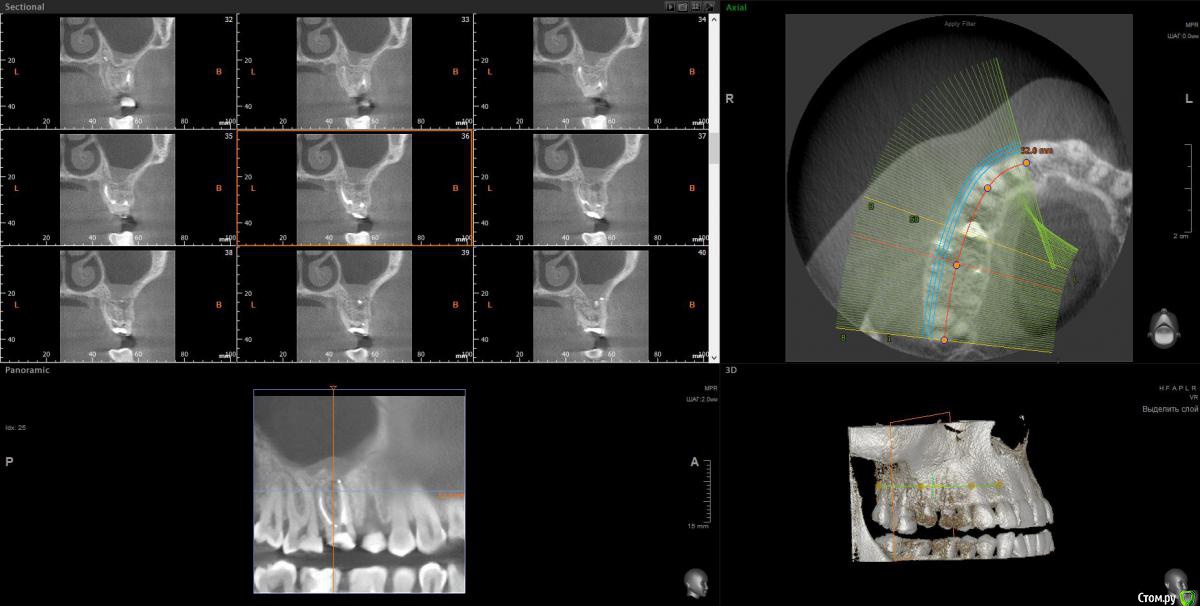

wladdX Опубликовано 2 февраля, 2017 Поделиться Опубликовано 2 февраля, 2017 Несколько скриншотов на скорую руку. Ссылка на комментарий

Весна2009 Опубликовано 2 февраля, 2017 Автор Поделиться Опубликовано 2 февраля, 2017 Несколько скриншотов на скорую руку.Огромное Вам спасибо! Может быть, есть желающие прокомментировать снимки? Заранее спасибо Ссылка на комментарий